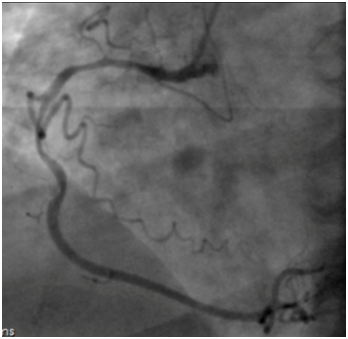

Coronary angiography revealed long, calcified > 40mm length lesion in right coronary artery proximal and middle part (Figure 1). Our decision was to treat this coronary lesion with BRS (Absorb BRS; Abbott Vascular, Santa Clara, CA, USA), following our centre plaque modification strategy, which is plaque modification before scaffold implantation using cutting or scoring balloon. In this case we used cutting balloon pre-dilatation 3.5x15mm 13 bars for each segment three times. Vessel dimensions were pre-analyzed with imaging methods to choose appropriate pre-dilatation balloon size. “PSP (Predilatation, Sizing, Post-dilatation) technique” that improves Absorb implantation is now widely described. Our centre following updated technique which is “IPSP (Imaging, Predilatation, Sizing, Postdilatation” technique. After plaque modification three BRS were implanted with total length 68mm. All scaffolds were implanted with small overlap to avoid uncovered gap which can provoke flow disturbances and possible future problems. Scaffold diameter was 3.5mm. An optimal scaffold apposition to vessel wall was achieved with non-compliant balloon 4.0x20mm. Post-dilatation was done with 15 bars in each segment. Mandatory for this intervention are imaging methods – intravascular ultrasound (IVUS) and optical coherence tomography (OCT). IVUS was performed before PCI, after plaque modification and after BRS implantation (Figure 2). OCT was performed after BRS implantation (Figure 3). Final angiography showed good result of procedure (Figure 4). Patient discharged next day on dual anti-platelet therapy for two years. Now patient reached six-month clinical follow-up with no cardiovascular events or bleeding.

Figure 4 Final angiography image for right coronary artery with good scaffold apposition.